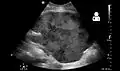

Imaging

Post operatively, kidneys are periodically assessed by ultrasound to assess for the imaging and physiologic changes that accompany transplant rejection. Imaging also allows evaluation of supportive structures such as the anastomosed transplant artery, vein, and ureter, to ensure they are stable in appearance.

The major sonographic scale in quantitative ultrasound assessment is with a multipoint assessment of the resistive index (RI), beginning at the main renal artery and vein and ending at the arcuate vessels. It is calculated as follows:

- RI = (peak systolic velocity – end diastolic velocity ) / peak systolic velocity

The normal value is ≈ 0.60, with 0.70 being the upper limits of normal.[63][64]

- Postoperative bleeding following kidney transplant as seen on ultrasound[78]

Postoperative bleeding following kidney transplant as seen on ultrasound[78]